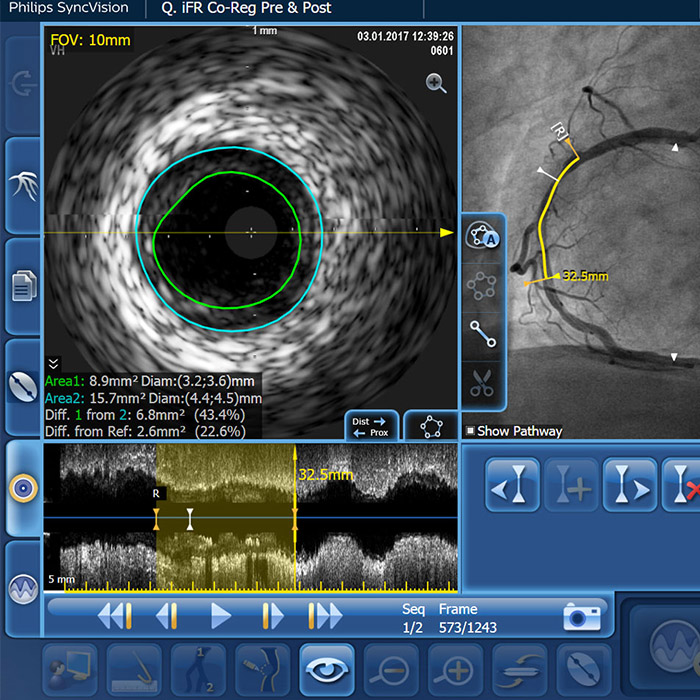

IVUS-guided vs. angiography-guided outcomes3